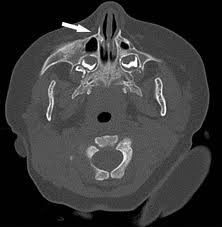

This rare birth defect is also known as PAS, in medical terminology. Pyriform aperture stenosis is a condition in which the anterior side of the nose is constricted. The bone in the upper jaw has abnormal growth. Abnormalities of the pituitary gland and single incisor tooth are associated with pyriform aperture stenosis sometimes.

The normal nasal airway has a bony inlet which is the smallest part known as pyriform aperture. Nasal airway resistance is increased, even if there are any minute changes in that area. Moreover, the anterior bony nasal apertures are narrow, which makes breathing difficult.